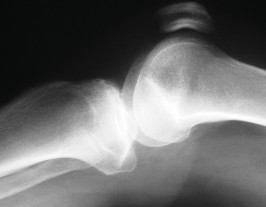

الأشعة السينية العادية (Plain Radiographs):

- المنظر الأمامي الخلفي (AP): يُظهر الركبة من الأمام.

- المنظر الجانبي (Lateral): يُظهر الركبة من الجانب.

- المنظر الخلفي الأمامي المثني (PA Flexed): يسمح بتقييم أفضل للجزء الخلفي من الركبة وقد يكشف عن تغيرات أكبر في الحجرة الخلفية الوحشية.

- منظر شروق الشمس (Sunrise/Patellofemoral): لتقييم المفصل الرضفي الفخذي.

- الأشعة السينية الطويلة للطرف السفلي بالكامل (Full-length standing radiographs): من الورك إلى الكاحل، وهي مفيدة جدًا، خاصة إذا تم استخدام تقنيات الملاحة الحاسوبية. تُظهر هذه الأشعة المحاذاة الكلية للطرف السفلي.